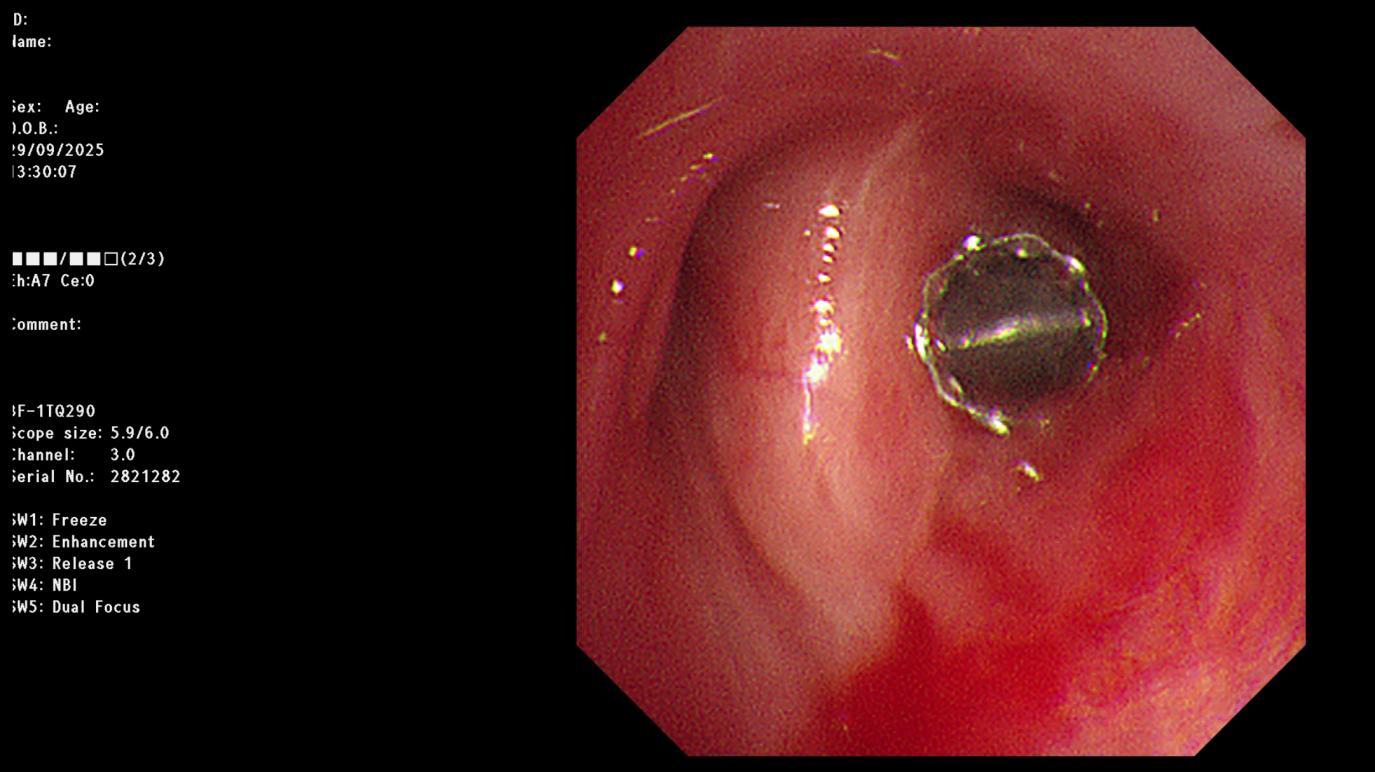

在明确治疗方案并与患者及家属充分沟通后,丁明团队决定实施经支气管镜EBV活瓣封堵术。手术在气管镜引导下进行,根据术前测量的结果,术中仅通过气管镜工作通道便将输送导管准确送到目标支气管,然后推动推送器将一枚直径4毫米的活瓣精准置入右上叶后段支气管开口。

这枚形似“鱼嘴”的活瓣暗藏玄机:它能随呼吸周期实现单向闭合,吸气时严密关闭阻止气体进入瘘口区域,呼气时则自动打开允许气体排出,形成“只出不进”的气流模式,从而维持胸腔负压,为瘘口愈合创造条件。置入瞬间,医护人员便观察到引流瓶水柱停止波动——这意味着漏气已即刻终止。

图为置入活瓣后